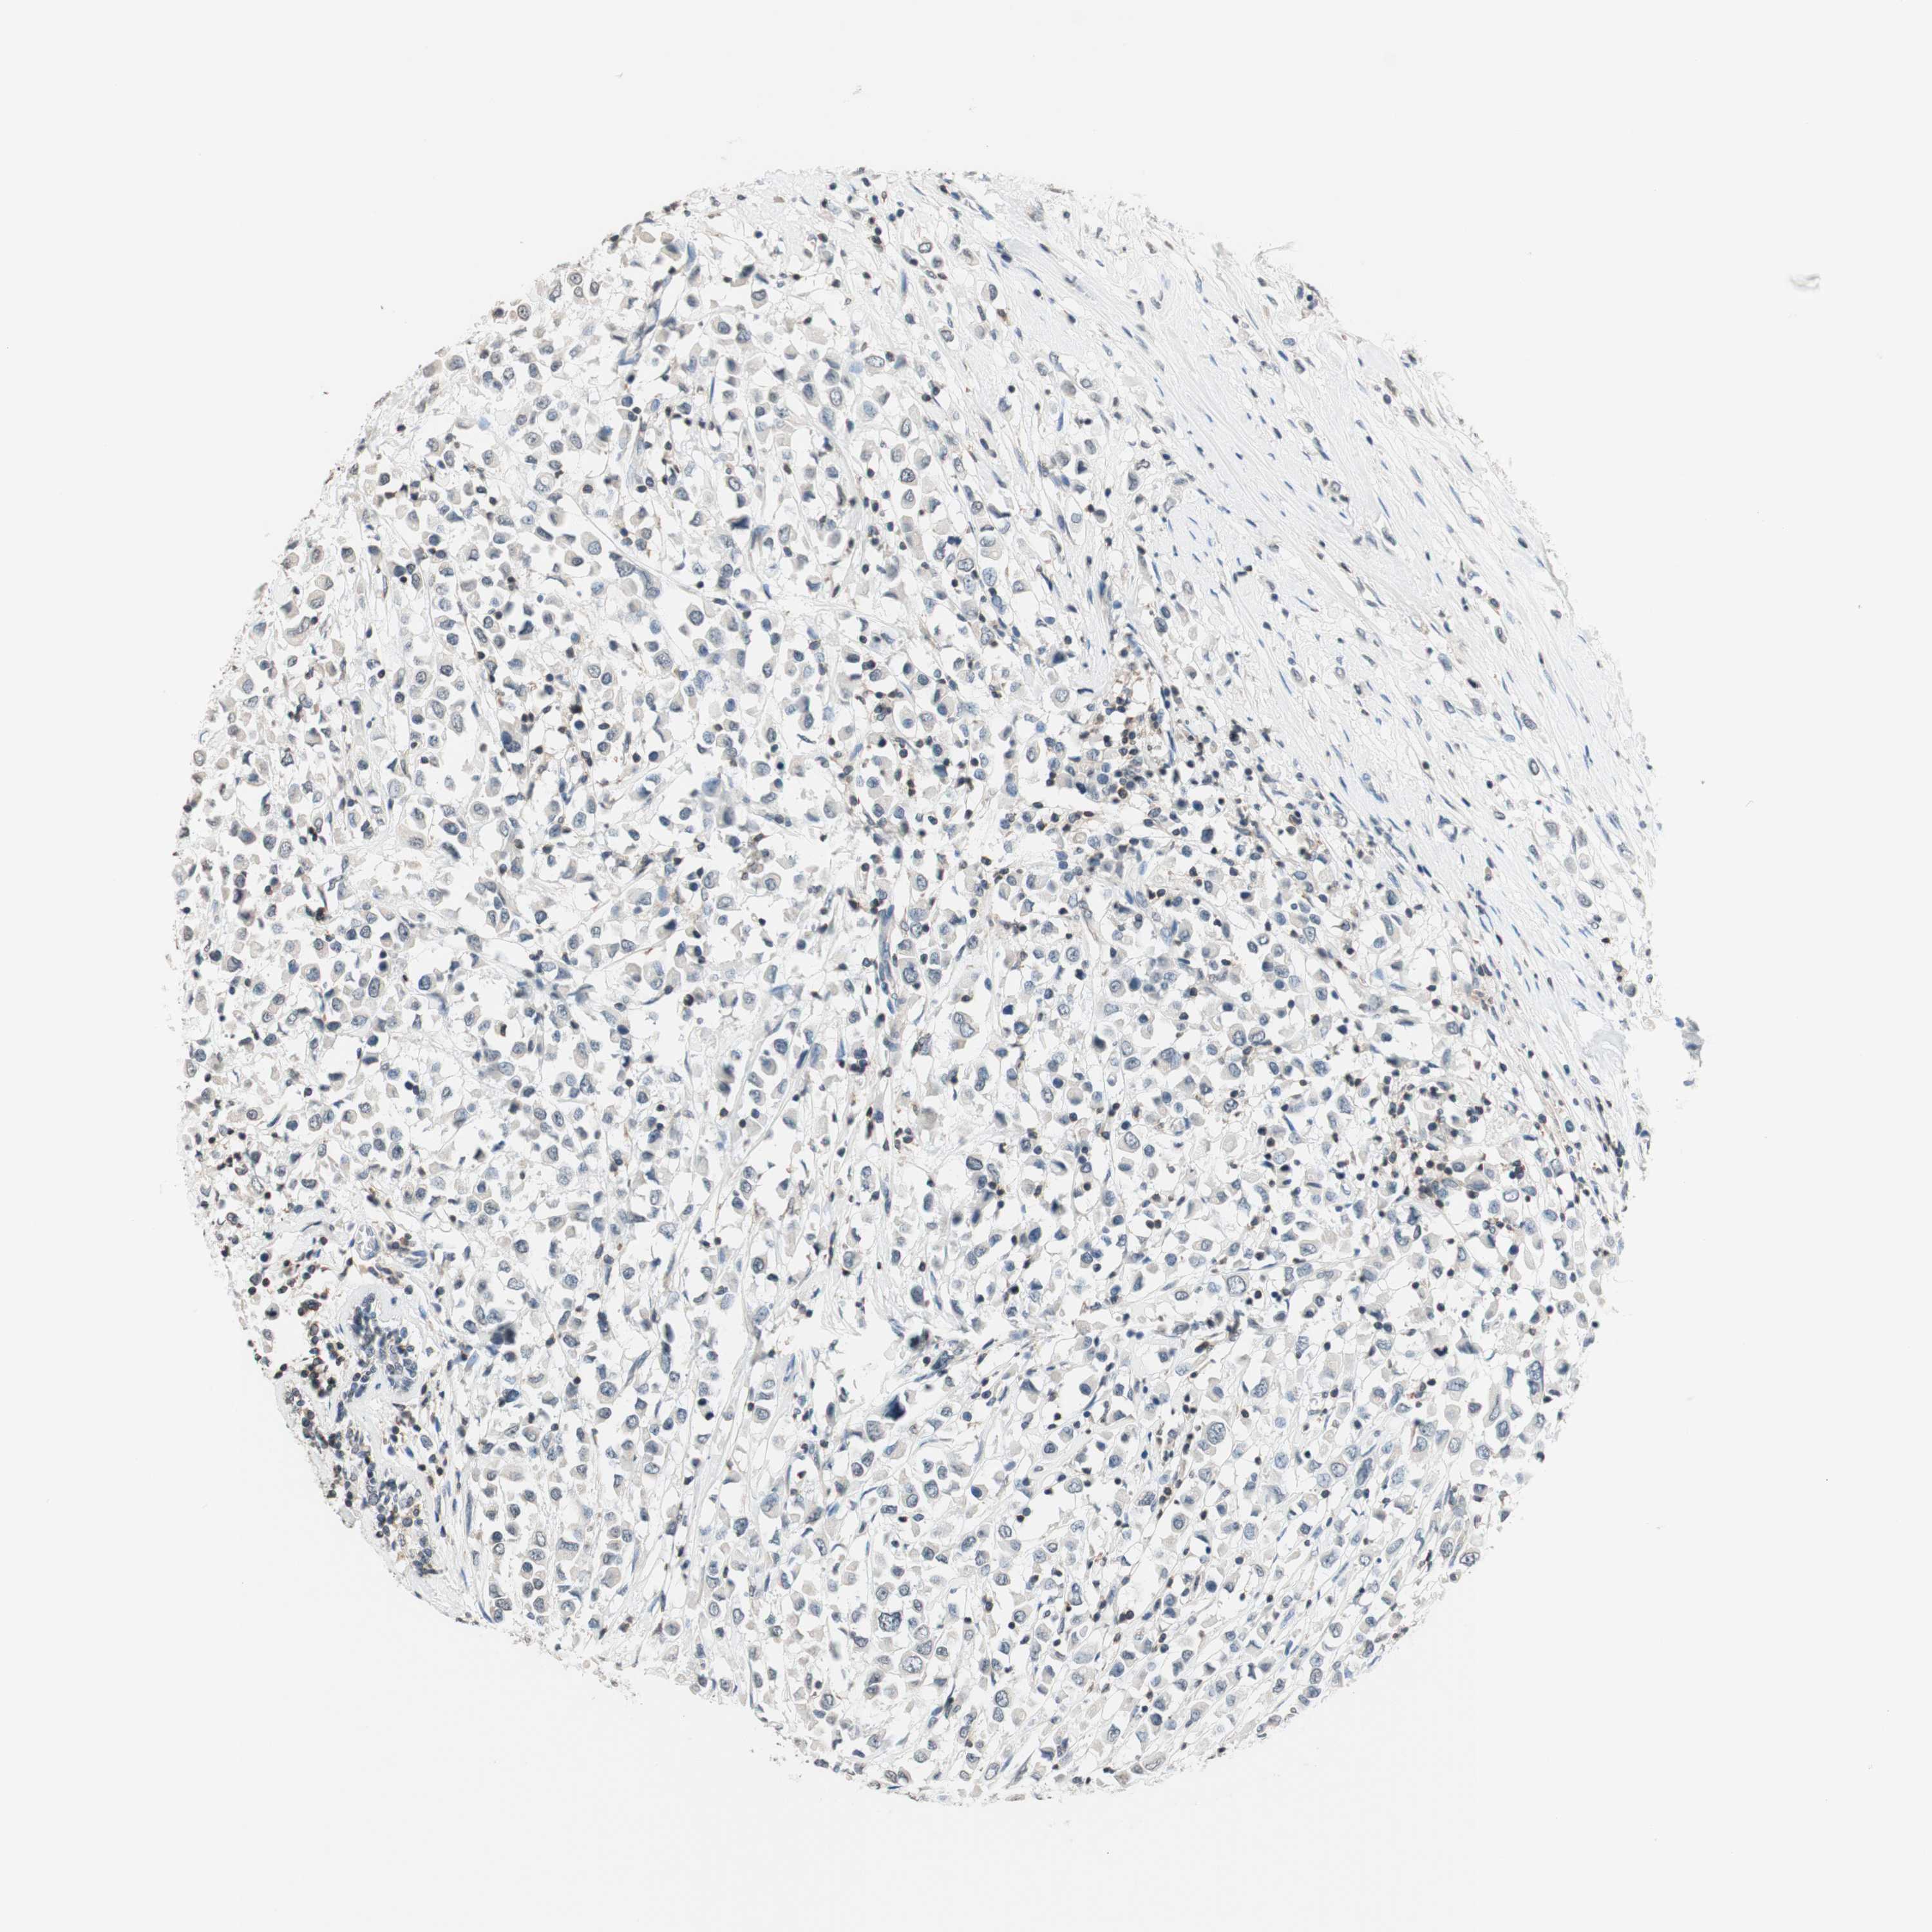

BRCA TCGA BRCA VALIDATION PROTEIN EXPRESSION

ANTIBODIES

AND

VALIDATION